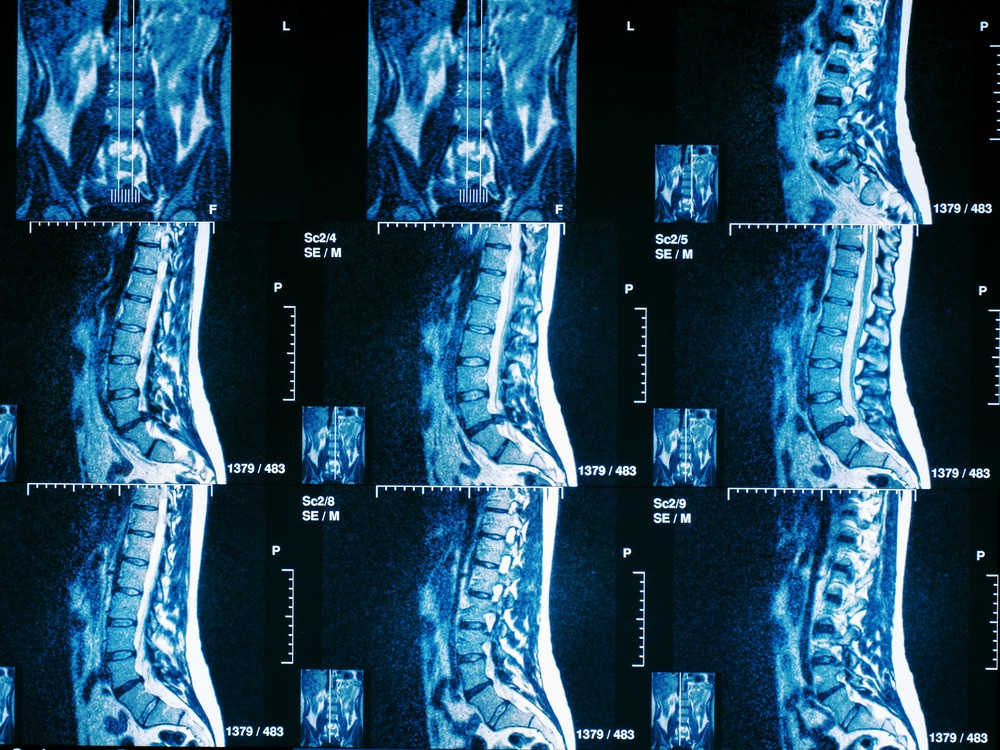

МРТ грудного отдела позвоночника. Грыжи дисков, секвестр. Разбор случая с пояснениями врача.

Обратите внимание на симметрию позвонков и дисков, чтобы выявить возможные отклонения.

Ищите участки с измененной плотностью тканей, которые могут указывать на патологии.

Используйте снимки в разных проекциях, чтобы получить более полное представление о состоянии позвоночника.

Сравнивайте снимки с нормальными изображениями, чтобы выявить аномалии.

Обратите внимание на состояние межпозвоночных дисков, чтобы оценить наличие протрузий или грыж.